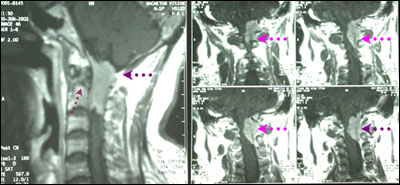

术后患者麻木症状消失,未再出现呼吸困难。顺利出院。

术后图片

专家评点:枕大孔区肿瘤如不及时采取手术治疗,患者会因呼吸肌无力最终导致呼吸停止而死亡。所以确诊后应限期手术。脑、脊膜瘤手术难度大,血运丰富,对术者要求较高。术后需注意稳定性。